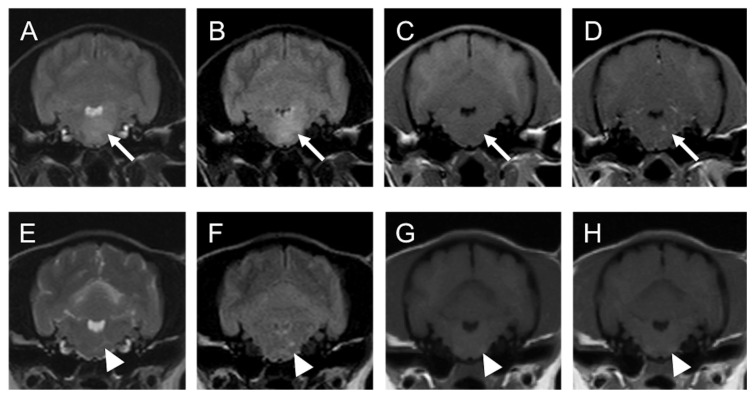

Химиотерапия (чаще всего протоколы с включением цитостатиков, проникающих через ГЭБ, например, высокие дозы цитозина-арабинозида, ломустин, протоколы типа CHOP) при лимфоме ЦНС может приводить к драматическому улучшению визуализации. Полная регрессия опухоли на МРТ – достижимая цель. В недавнем сообщении из Японии две собаки с PCNSL получали комбинацию нимустина (нитрозомочевина, аналог ломустина) и преднизолона: у них через несколько месяцев лечения неврологические симптомы полностью регрессировали, а контрольная МРТ показала исчезновение контрастируемых очаговpmc.ncbi.nlm.nih.govpmc.ncbi.nlm.nih.gov. На месте бывших поражений остались лишь небольшие участки повышенного T2-сигнала без накопления контраста, расцененные как глиоз (рубцовые изменения)pmc.ncbi.nlm.nih.govpmc.ncbi.nlm.nih.gov. Ремиссия сохранялась длительно – в одном случае собака прожила свыше 7 лет без рецидиваpmc.ncbi.nlm.nih.gov. Такой поразительный ответ подтверждает, что лимфома – опухоль радиочувствительная и хемочувствительная. На практике это означает, что МРТ «до и после» лечения может разительно отличаться: было объемное поражение с отеком – стало почти нормальное изображение мозга (рис. 1).

Кейс 1. Собака, 3 года, генерализованная лимфома ЦНС. Пациент – той-пудель с остро возникшим синдромом вестибулярного поражения и глубокими расстройствами проприоцепцииpmc.ncbi.nlm.nih.gov. На МРТ выявлены множественные очаги: в левом таламусе и в продолговатом мозге – оба гиперинтенсивны на T2/FLAIR и слегка накапливают контрастpmc.ncbi.nlm.nih.gov. Также отмечается диффузное усиление мягких мозговых оболочек над этими областями. ЦСЖ-аналіз показал повышенный клеточный состав с моноцлональными В-лимфоцитамиpmc.ncbi.nlm.nih.gov. Диагноз – PCNSL, В-клеточный. Назначена химиотерапия (нимустин + преднизолон). Через 8 месяцев контрольная МРТ: все прежние очаги полностью исчезли, остались лишь точечные зоны глиоза без контрастированияpmc.ncbi.nlm.nih.govpmc.ncbi.nlm.nih.gov. Клинически – полная ремиссия, которая сохраняется свыше 2 лет (данные на момент публикации)pmc.ncbi.nlm.nih.gov.